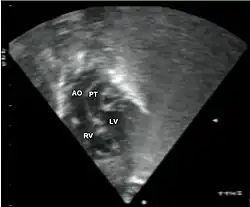

- Echocardiogram: An echocardiogram is an ultrasound of the heart that accurately assesses the heart’s structure and function, and can show the specific features of TGA, if present. This imaging modality allows for the definitive diagnosis of TGA to be made.[3]

Additional images